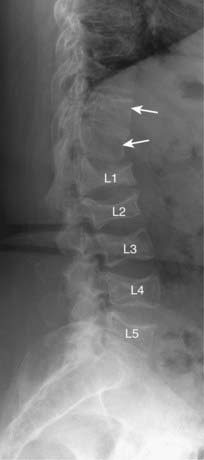

Figure 24-10 Compression fractures secondary to osteoporosis.

Vertebral compression fractures are common, affecting women more than men, and typically secondary to osteoporosis. Osteoporotic compression fractures usually involve the anterior and superior aspects of the vertebral body sparing the posterior aspect (solid white arrows). This produces a wedge-shaped deformity that leads to accentuation of the kyphosis in the thoracic spine. Progressive loss of overall body height is a common finding with compression fractures in the elderly.

image Vertebral compression fractures are common, affecting women more than men, and typically secondary to osteoporosis. They may be asymptomatic or they may produce pain in the midthoracic or upper lumbar area that typically disappears in 4 to 6 weeks. Sometimes they are first noticed because of increasing kyphosis or loss of overall body height.

imageOsteoporotic compression fractures usually involve the anterior and superior aspects of the vertebral body sparing the posterior body. There will usually be a difference in the height between the anterior and posterior aspects of the same vertebral body in excess of 3 mm. Alternatively, the compressed body is typically >20% shorter than the body above or below it.

image This compression pattern produces a wedge-shaped deformity that leads to accentuation of the normal kyphosis in the thoracic spine (the so-called dowager’s hump) (Fig. 24-10).